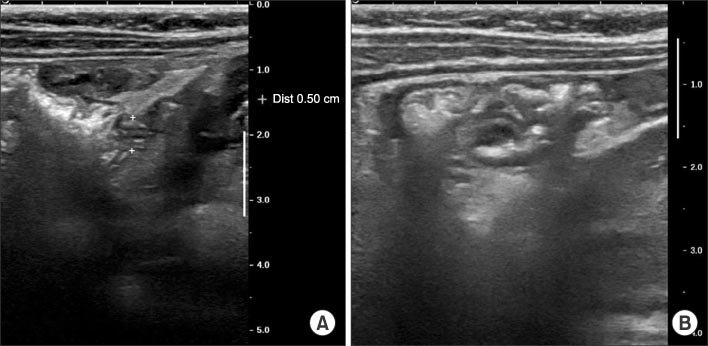

Fig. 5

White arrowhead indicates intestinal tissue; Black arrowhead indicates gastric tissue; Black arrow indicates serosa tissue and inflammation (H&E, ×40).

Fig. 5 White arrowhead indicates intestinal tissue; Black arrowhead indicates gastric tissue; Black arrow indicates serosa tissue and inflammation (H&E, ×40).